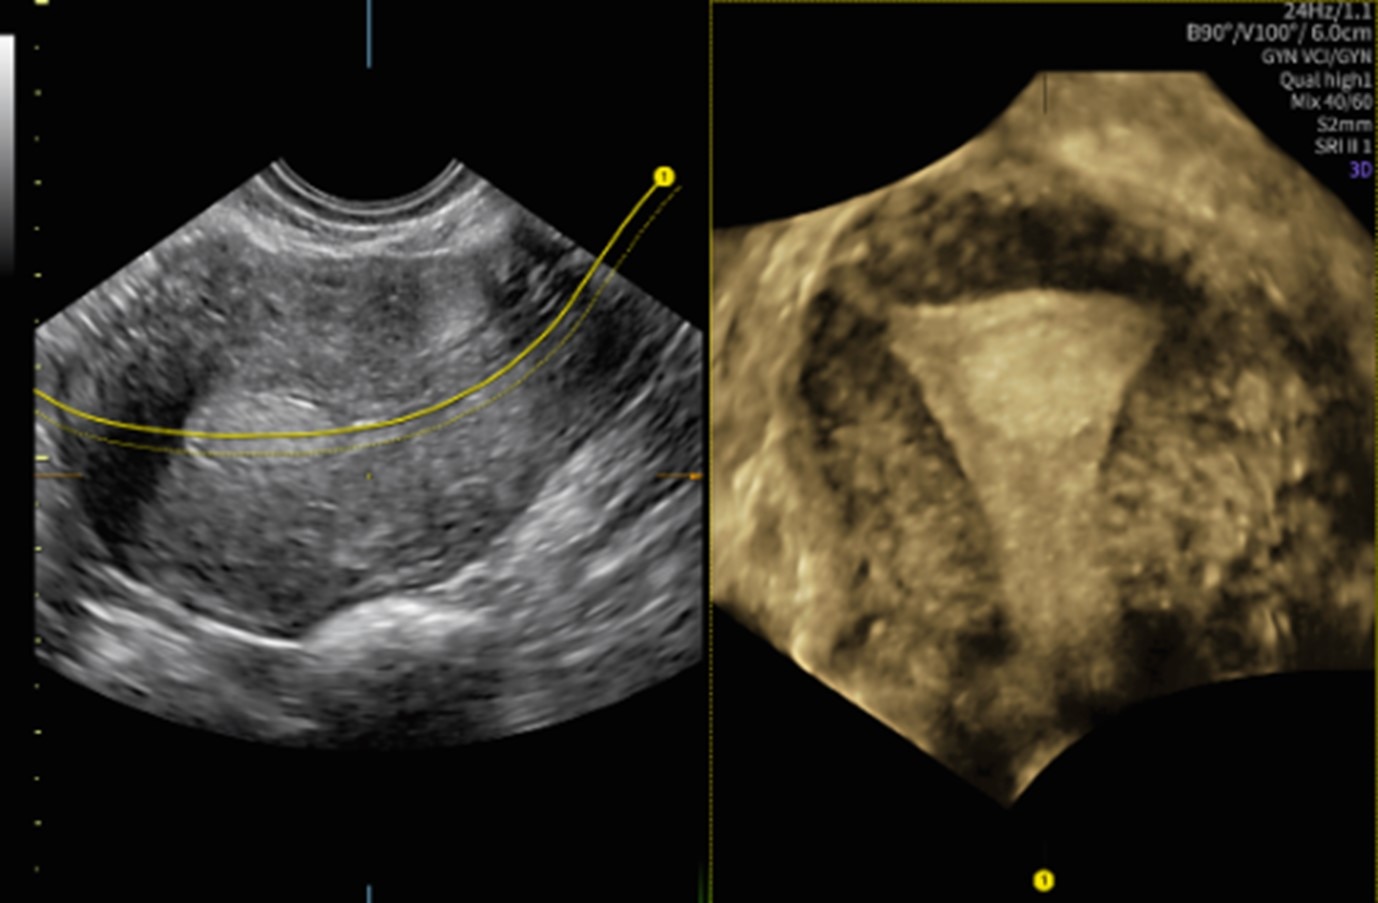

【画像】ラインを引くだけで子宮の断面を自動表示するUterine Traceは、子宮形態の把握に役立つ